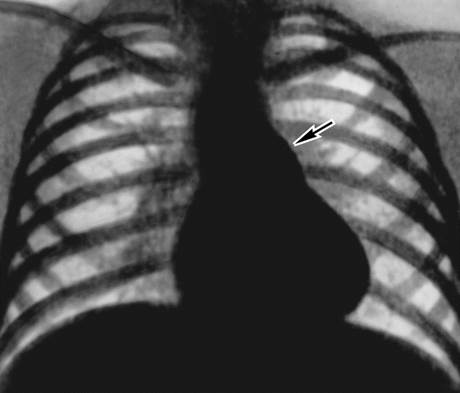

Для подтверждения диагноза назначают рентгенографию, которая позволяет увидеть изменения в легочной ткани и сосудистом пучке. Также проводятся УЗИ и эхокардиография, которые помогают выявить гипертрофию левого желудочка сердца и определить направление сброса крови.

- Рентгенография помогает оценить размер сердца и выявить повреждения легочной ткани.

| Одышка | Рентгенография грудной клетки (расширение легочных сосудов) | Катетерная эмболизация |